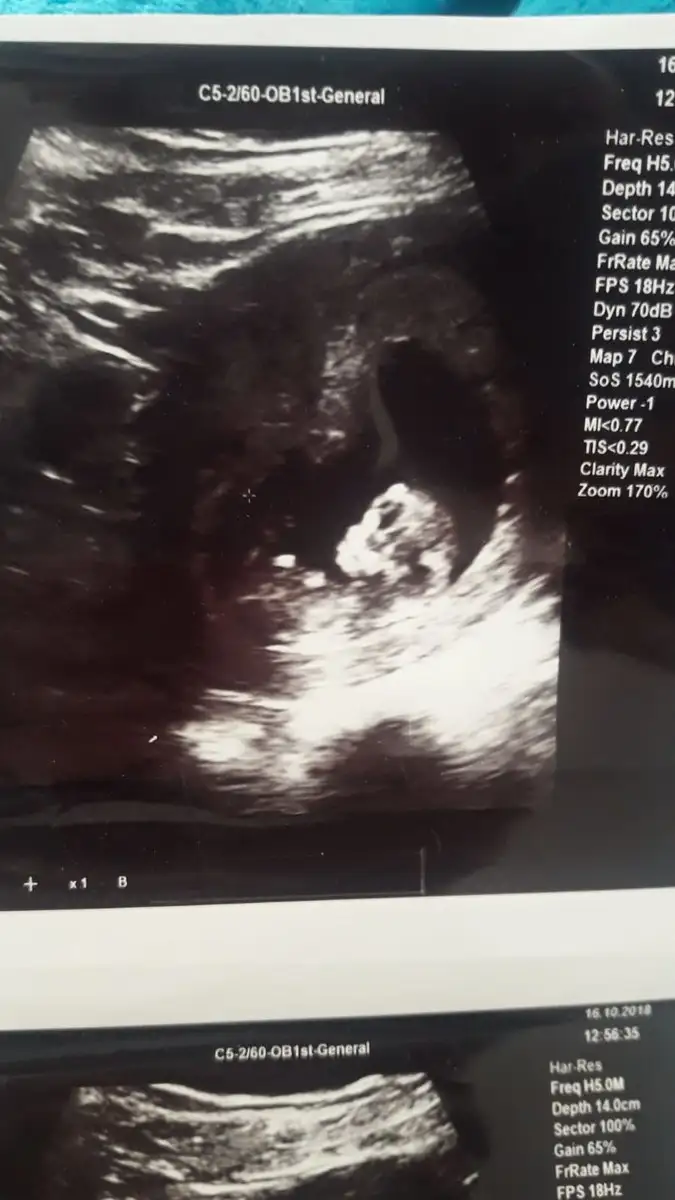

Ya minik şey seni kafasina bak ♥️

Maşallah nasılda güzel annesi..

Erkek gibi hissettim benzettim ben. Sağlıcakla gelsin ♥️

Dr da erkege benziyor ama tam belli degil ilerleyen haftalarda bakariz dedi .

Ben erkeğe benzettim :) kaç haftalık bebeğin canım maşallah nasıl güzel bizde görürüz inşallah böyle büyüdüğünü :)

14 haftalik canim ama devlette biraz daha ileri cikti . Ozel doktoruma gore soyluyorum. Insallah canim. Insallah tez vakitte sizde saglik ve hayirlisi ile gorursunuz . Ve hepimiz de kucagimiza hayirlisi ve saglikla aliriz insallah . Erkege kiza nasil benzetiyosunuz o kadar baktim nesinden anliyosunuz :))))